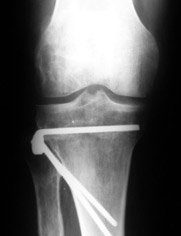

Уважаемые коллеги, много работ посвящено коррекции деформаций конечностей (варусной, вальгусной, торсионной), НЕ ВАЖЕН способ фиксации, важен подход – правильная биомеханическая коррекция, что достигается правильным определением уровня деформации (бедро, голень) и соответственно, правильным определением уровня коррекции.

Аппаратная коррекция очень грамотно изложена в диссертации Белокрылова Николая Михайловича «Хирургическая тактика лечения деформирующего гонартроза» Пермь 1998г. В моей работе описаны методы коррекции с накостным остеосинтезом. «Корригирующие операции в лечении гонартроза» Москва 2003г.